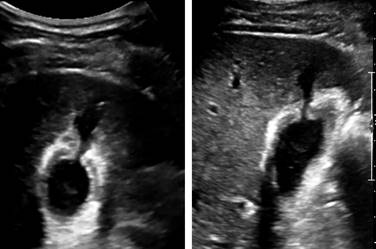

Se realiza USG de control que reportó vesícula biliar con paredes engrosadas hasta 8 mm, edema perivesicular, a nivel del fondo pérdida de la continuidad donde discurre líquido de aspecto hipoecoico similar a contenido vesicular de 3.2 cm3 (hemobilia), sin evidencia de líquido libre en cavidad abdominopélvica (Figura 5).

Figura 5: Imágenes de ultrasonido en las que se observa solución de la continuidad de la pared posterior de la vesícula, engrosamiento y edema de la pared vesicular.